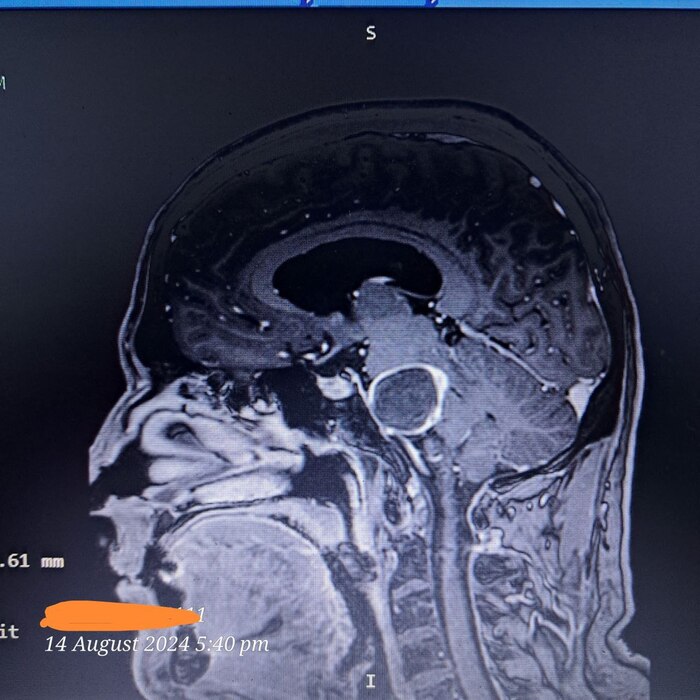

Уже 4.5дня живу с трубкой. Из мозга в живот. Пожизненно!

Четко виден профиль трубки, как украшение лысому))) толстая, эт здорово, надежно.

Следующая операция, удаление кисты у ствола мозга, что идет в позвоночник. Жду.

Кто не знает, мне дня 3-4 назад поставили трубку сливную подкожную пожизненную из черепной коробки в брюшную полость для сброса излишнего давления. и вот я уже киборг)))

Это виден шарик 3 см кисты у ствола мозга. С ним хожу, работаю